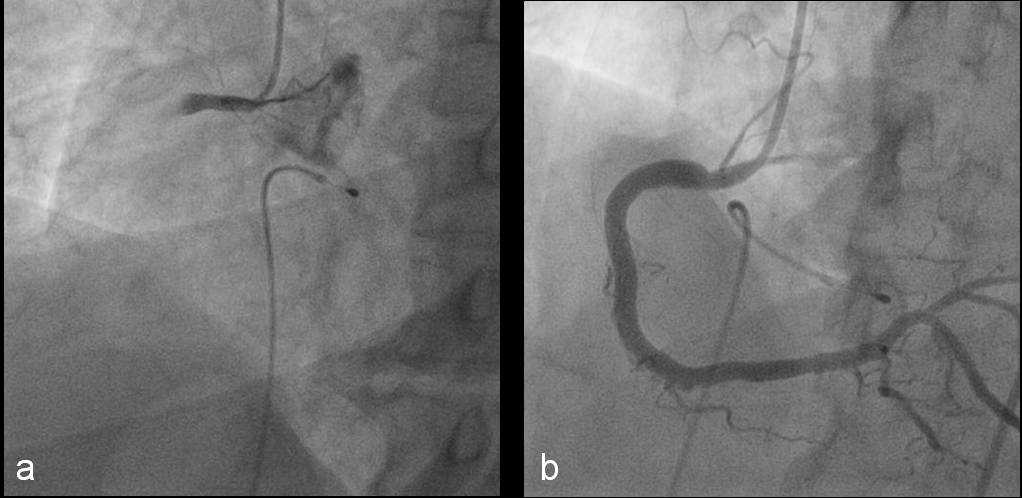

La injectarea in artera coronara dreapta se evidentiaza ocluzie in segmentul I cu aspect de tromb intraluminal (figura 3a). Avand in vedere spasmul de la nivelul arterei coronare stangi se administreaza repetat nitroglicerina intracoronarian cu disparitia completa a spasmului la nivelul intregului vas (figura 3b).